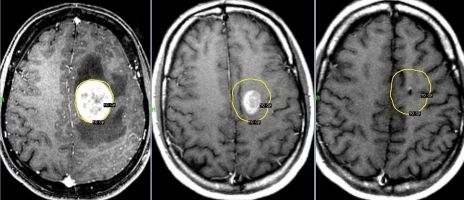

При поверхневих доброякісних пухлинах (остеома), можливе видалення тільки самої пухлини зі збереженням внутрішніх ділянок кістки. При злоякісних пухлинах необхідна максимально радикальна резекція пухлини кісток черепа з резекцією межуючих з пухлиною ділянок кістки.

Під загальним наркозом біля краю пухлини фрезою фірми Stryker накладається невеликий отвір, через який спеціальними борами та фрезами пухлина видаляється від кістки голови.

При наявності проростання пухлини в порожнину черепа виконується додаткове видалення тканини пухлини кісток черепа зі збереженням мозкової тканини та пластики оболонок головного мозку спеціальними матеріалами. При цьому використовуємо мікроскоп Carl Zeiss.

Після резекції пухлини кісток черепа, робимо пластику утвореного дефекту кістки спеціальною титановою сіткою, кістковим цементом.